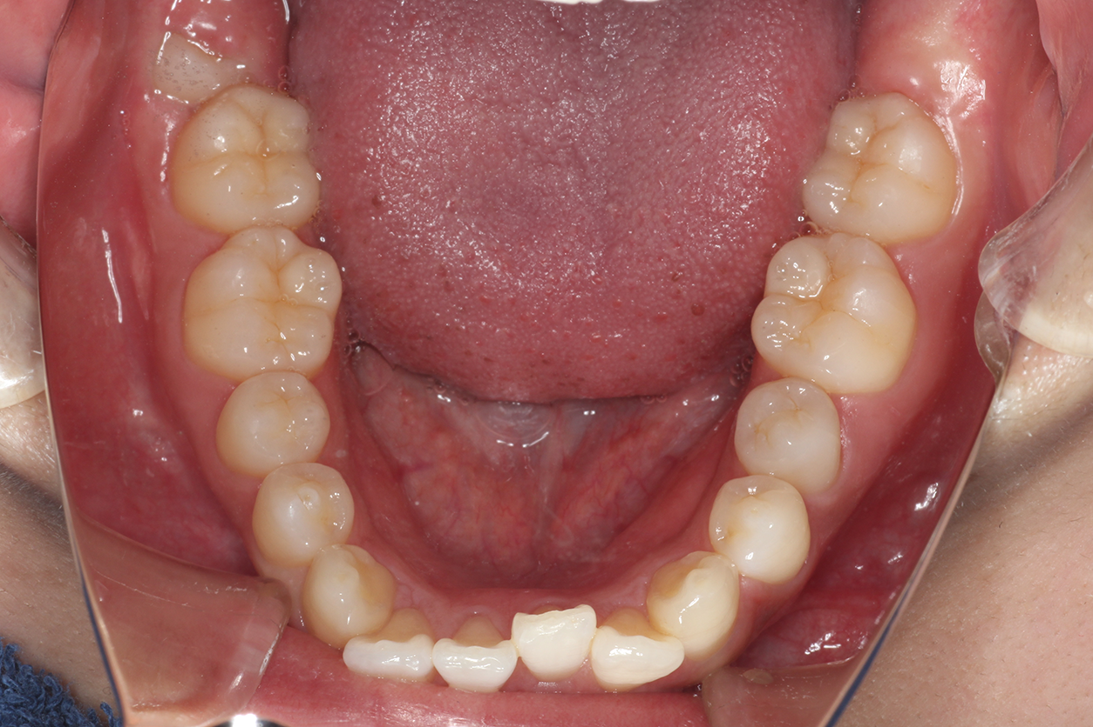

• 治療前

• 治療後

主訴:前歯が出ている

診断:叢生、上顎前突

治療内容:唇側矯正治療

年齢:22歳

治療に用いた装置:マルチブラケット装置

抜歯or非抜歯:抜歯(上下顎両側小臼歯)

期間:20ヶ月

回数:20回

費用:990,000円(税込)

リスク・副作用:虫歯、歯肉炎、歯肉退縮、歯根吸収、後戻りなど